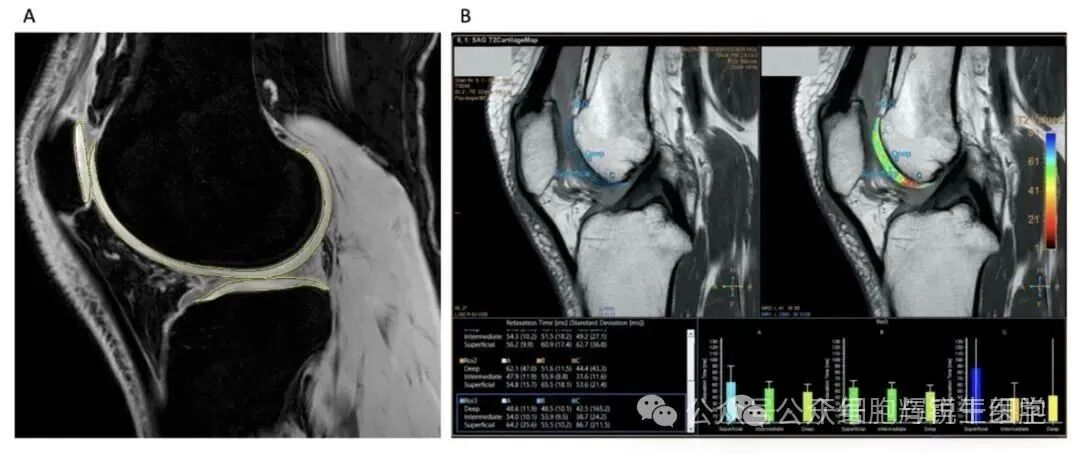

定量MRI分析软骨变化

在疾病改善定量评估中,该疗法也在改善软骨体积和质量方面显示出积极的作用。综合来看,或提示MSCs疗法有延迟或预防TKR手术的潜能。